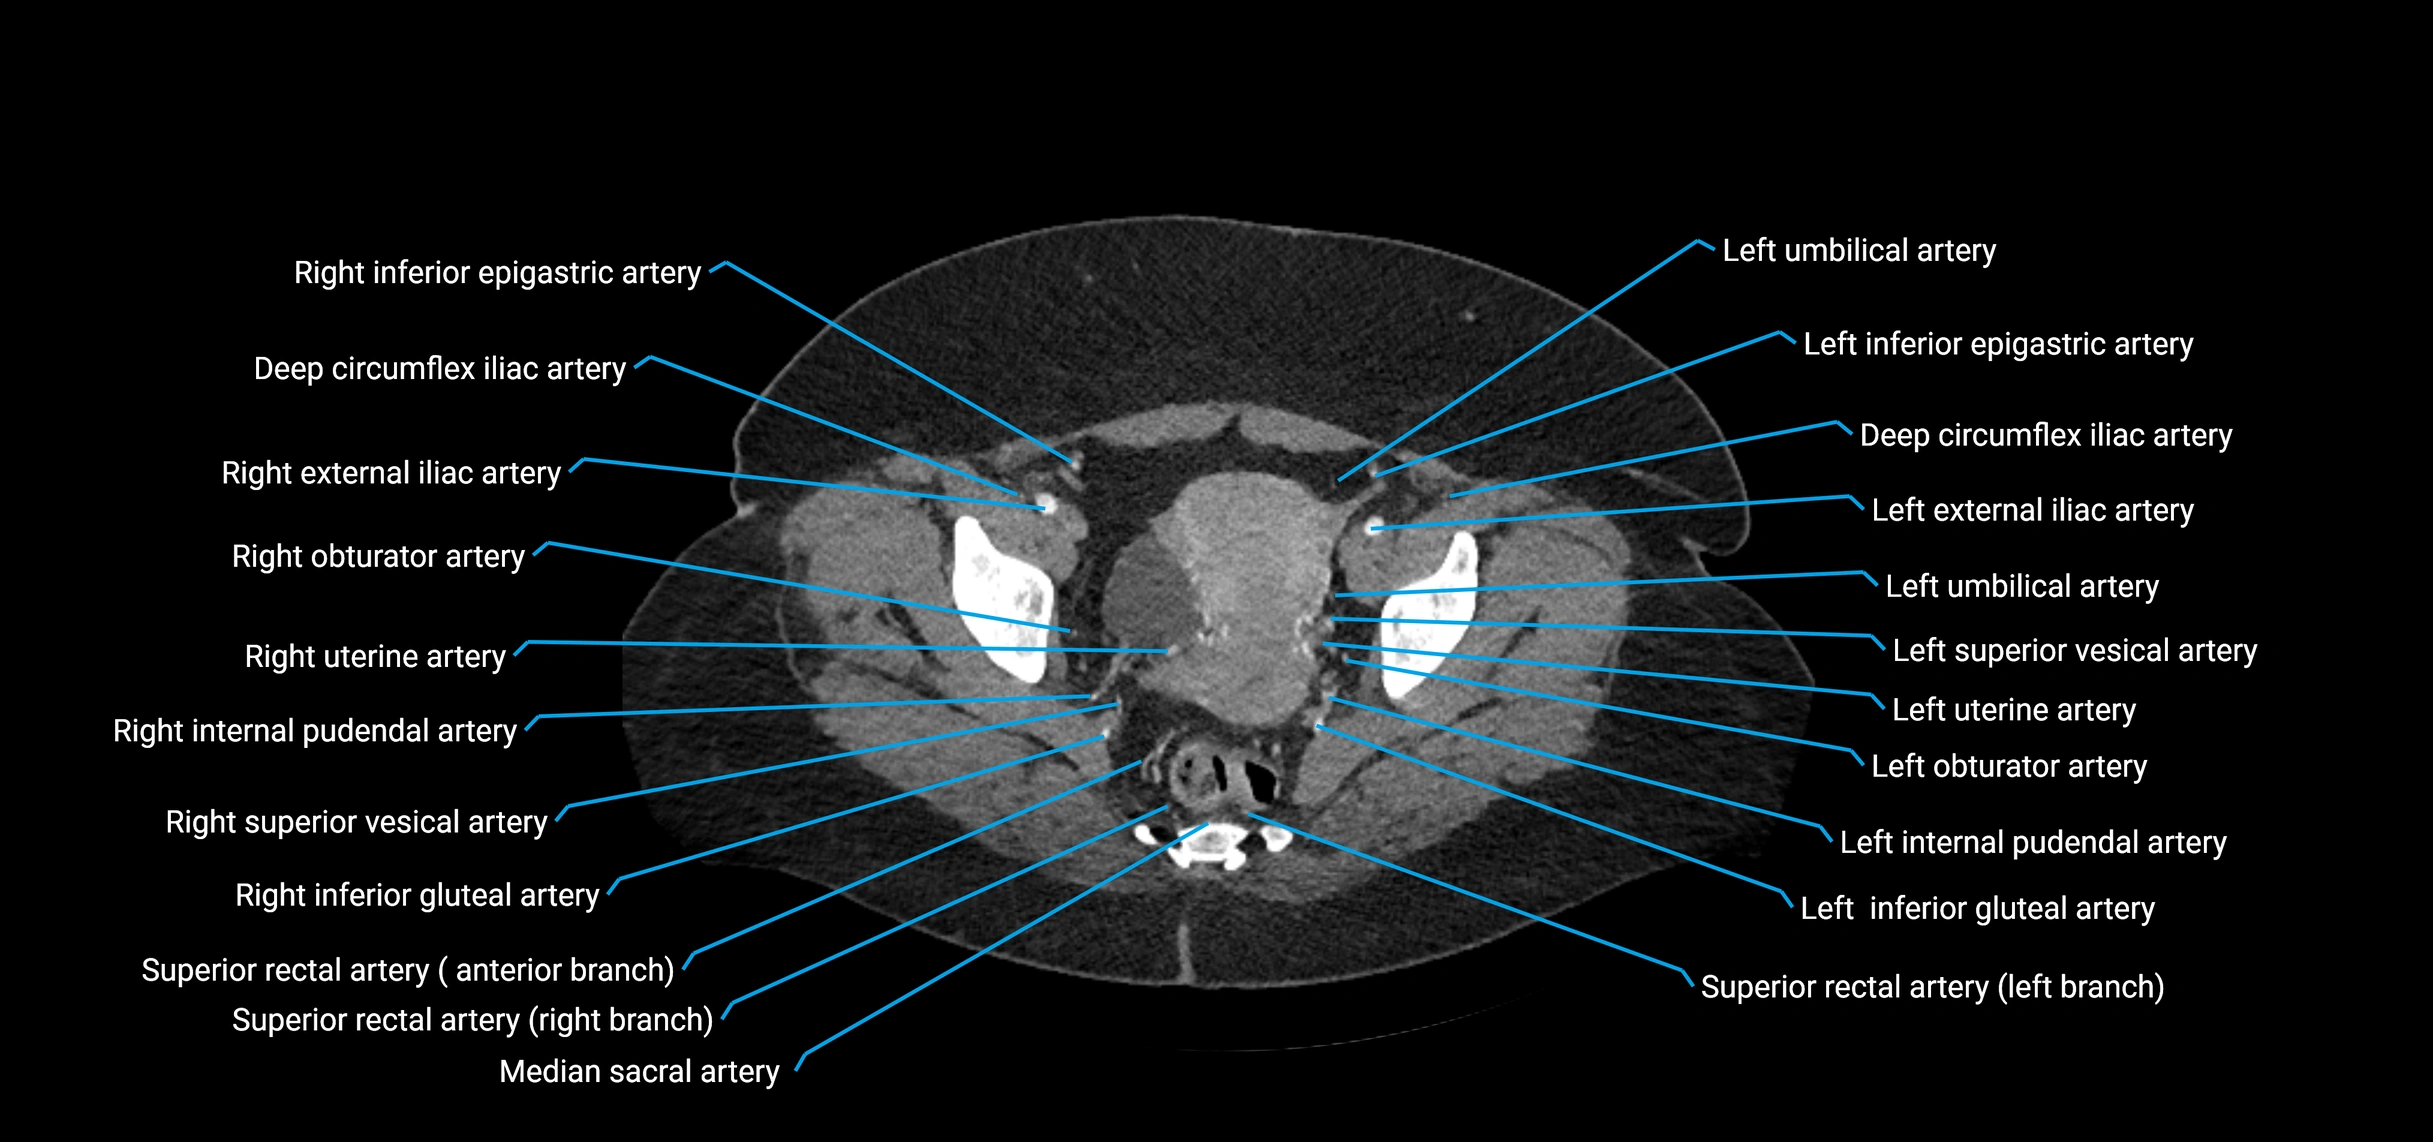

• Terminal branches: right and left common iliac arteries

CT images

image